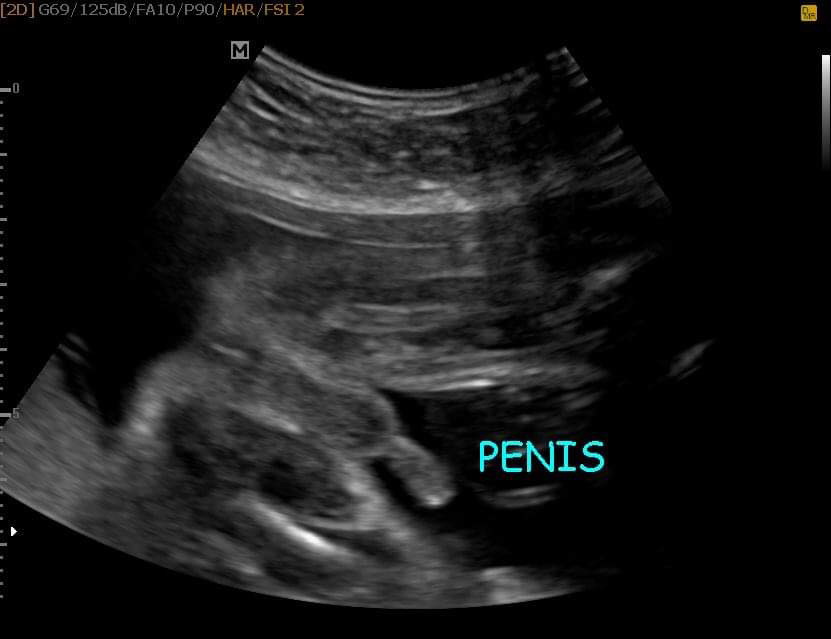

มีแท่งคร่าบบบบบ

หมอบอกผู้ชายค่ะ

เรามีแท่งน้อยๆ 56

ผมมีเเท่งคับ🤣🤣